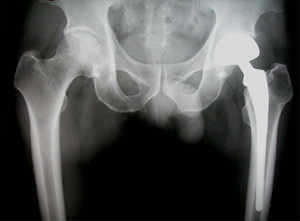

상기 환자는 46년 전부터 고관절 통증이 있었으며, 12년전 Lt. total hip replacement(THR)을 받은 분으로 2년 전부터 통증으로 인해 물리치료를 받았지만 통증이 지속되었고, 본원 OS 외래에서 방사선 촬영하여 Lt. THR loosening 소견으로 revision O.P. 위해 입원하여 O.P.이후 재활위해 물리치료실로 의뢰됨

• 고관절 치환술 후 X-선 고관절 치환술 후 X-선 사진